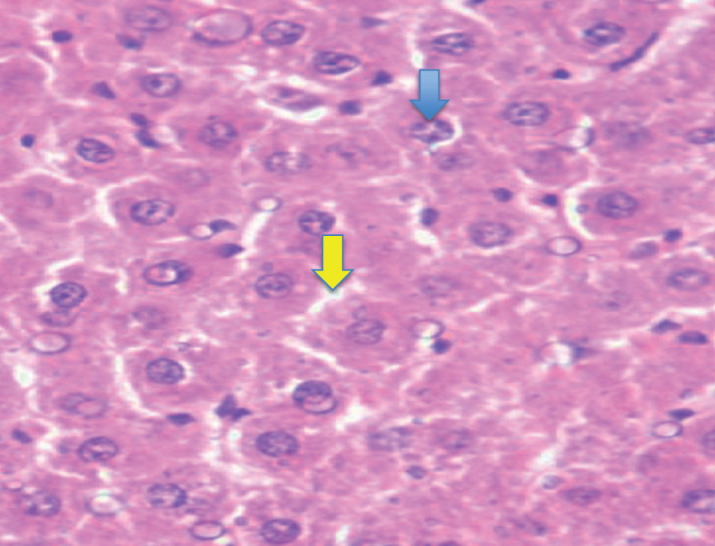

Results: The results revealed the efficacy of the diabetic model. All biochemical investigations were significantly higher in the diabetic group compared with that of control group (p<0.001). Histological studies showed the existence of morphological alterations in cells and fatty changes in the diabetic group compared with the control group. The expression of Ki67 was significantly higher in the diabetic group compared with that in the control group (p=0.011).